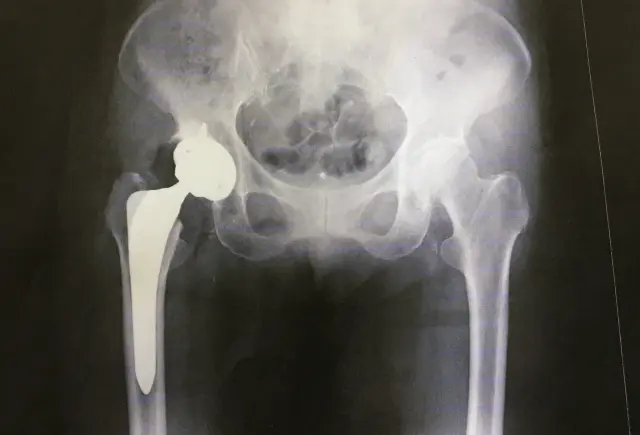

整形外科では股関節の状態を把握するために、まずレントゲン検査が行われることがほとんどです。この画像検査では骨の形や関節の隙間、骨の密度などを確認することができ、医師はこれらの情報をもとに現在の進行度を判断しています。レントゲン写真に写る特徴的なサインを理解することで、あなた自身の状態をより深く把握できるようになるでしょう。

股関節のレントゲン撮影では、骨盤と大腿骨の位置関係や軟骨の厚み、骨の形状変化などが細かくチェックされます。軟骨自体はレントゲンには写りませんが、骨と骨の間の隙間を見ることで軟骨がどれくらい残っているかを推測することができるのです。この隙間が狭くなっていれば軟骨がすり減っている証拠となり、変形が進行していることを示しています。

画像所見から得られる情報は、今後の対応方針を決める上でとても重要な判断材料になります。保存的なアプローチで様子を見ていくのか、それとも手術を検討する段階なのか、レントゲン写真が教えてくれる情報は決して少なくありません。ただし画像で見える変形の程度と実際の痛みの強さは必ずしも一致しないことも覚えておいてください。

変形性股関節症のレントゲン写真には、いくつかの典型的なサインが現れます。これらのサインを知っておくことで、医師からの説明がより理解しやすくなるはずです。

関節裂隙という言葉を聞いたことがあるでしょうか。これは骨と骨の間にある隙間のことで、この部分に軟骨が存在しています。健康な股関節では一定の幅がある関節裂隙ですが、変形が進むと軟骨がすり減って隙間が狭くなっていきます。レントゲン写真では骨同士が近づいて見えるため、医師はこの狭小化の程度から進行度を判断しているのです。

初期の段階では部分的に狭くなっている程度ですが、進行すると関節全体で狭小化が見られるようになります。さらに末期になると隙間がほとんどなくなり、骨同士がほぼ接触している状態になってしまいます。この関節裂隙の狭小化は変形性股関節症を診断する上で最も重要な所見のひとつと言えるでしょう。

骨棘とは骨の縁にできるトゲのような突起のことで、関節に負担がかかり続けることで形成されます。体は関節を安定させようとして骨を増やそうとするのですが、この反応が骨棘として現れるのです。レントゲン写真では骨の輪郭が不規則になり、トゲトゲした印象を受けることがあります。

骨棘自体が直接痛みを引き起こすわけではありませんが、周囲の組織を刺激したり関節の動きを制限したりすることがあります。骨棘が大きくなると股関節の可動域が狭くなり、靴下を履く動作や足の爪を切る動作がしづらくなることも少なくありません。この骨棘の有無や大きさも、進行度を評価する際の重要な指標となっています。

レントゲン写真で骨が白く濃く写る部分を骨硬化像と呼びます。これは関節に加わる負担が増えたことで、骨が硬く密になった状態を示しています。特に体重がかかる部分の骨に見られることが多く、関節への負担が長期間続いていることのサインと言えるでしょう。

一方で骨嚢胞は骨の中にできる空洞のことで、レントゲンでは黒い丸や楕円形の影として写ります。関節の圧力が不均等になることで骨の内部に液体が溜まり、このような空洞が形成されると考えられています。骨硬化像と骨嚢胞はどちらも進行期以降に見られることが多い所見です。

変形性股関節症は一般的に初期、進行期、末期の3段階に分類されます。それぞれの段階でレントゲン写真に現れる特徴が異なるため、医師はこれらの所見を総合的に判断して現在の進行度を評価しています。

末期になると関節裂隙がほとんど消失し、骨同士がほぼ接触している状態になります。大きな骨棘や広範囲の骨硬化像、複数の骨嚢胞が確認され、股関節の変形が著しく進行していることがわかります。この段階では安静にしていても痛みがあったり、夜間痛で睡眠が妨げられたりすることも珍しくありません。